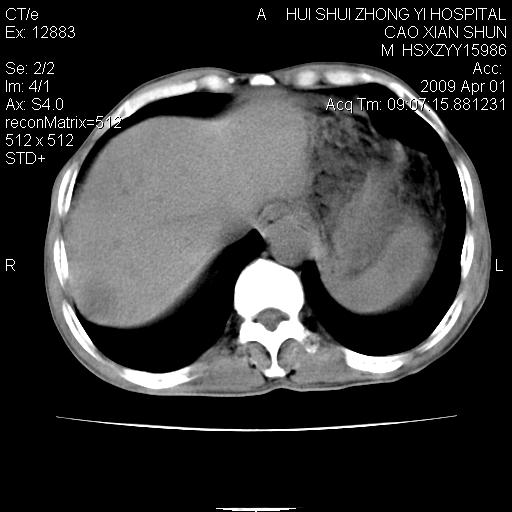

以下是引用随光逐影在2009-4-1 14:23:00的发言:[br]肝、脾多发低密度占位性病变,性质待定(不排除转移瘤可能);建议行进一步检查。

以下是引用liaoqiang在2009-4-1 15:53:00的发言:[br]考虑脾脏肿瘤或胰尾部肿瘤伴肝转移。建议增强。

以下是引用ydx_74在2009-4-1 15:18:00的发言:[br]肝、脾多发低密度占位性病变,考虑转移瘤或淋巴瘤